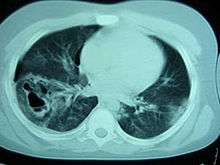

Computed tomography

Computed tomography (CT scanning) is a more sensitive test for pulmonary contusion,[6][33] and it can identify abdominal, chest, or other injuries that accompany the contusion.[38] In one study, chest X-ray detected pulmonary contusions in 16.3% of people with serious blunt trauma, while CT detected them in 31.2% of the same people.[45] Unlike X-ray, CT scanning can detect the contusion almost immediately after the injury.[43] However, in both X-ray and CT a contusion may become more visible over the first 24–48 hours after trauma as bleeding and edema into lung tissues progress.[46] CT scanning also helps determine the size of a contusion, which is useful in determining whether a patient needs mechanical ventilation; a larger volume of contused lung on CT scan is associated with an increased likelihood that ventilation will be needed.[43] CT scans also help differentiate between contusion and pulmonary hematoma, which may be difficult to tell apart otherwise.[47] However, pulmonary contusions that are visible on CT but not chest X-ray are usually not severe enough to affect outcome or treatment.[37]